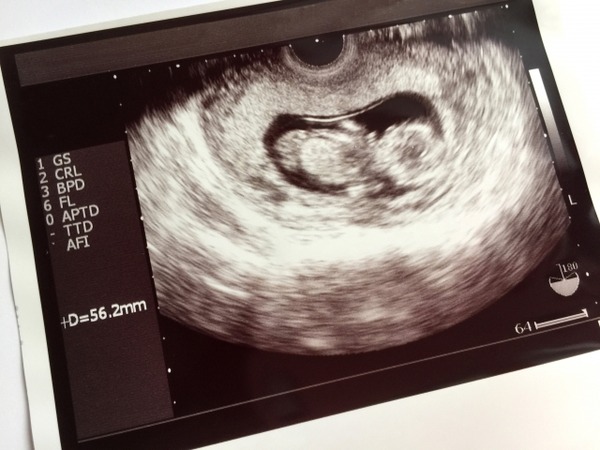

【悲報】嫁ちゃん(38歳)、「ダウン症を妊娠したみたい…」結果・・・・。 Twitter Facebook はてブ LINE コピー 2022.07.11 スポンサーリンク 1: 風吹けば名無し 2020/12/01(火) 14:27:43.70 ID:vudapw3/M ワイは堕ろせって言ってるが嫁ちゃんは誤診で正常かもしれなから産みたいだとさ 続きを読む